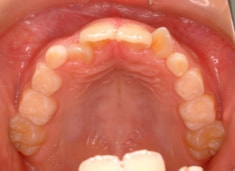

検査時のレントゲン分析では、上下顎の関係は、上顎の劣成長があり下顎前突傾向という値がでておりましたが、前歯ジャンプ後はフェイスマスクの効果もあり、上下顎の関係は正常化しています。

上顎が若干優位になっていますので、今後の下顎の成長のための貯金になっているくらいです。